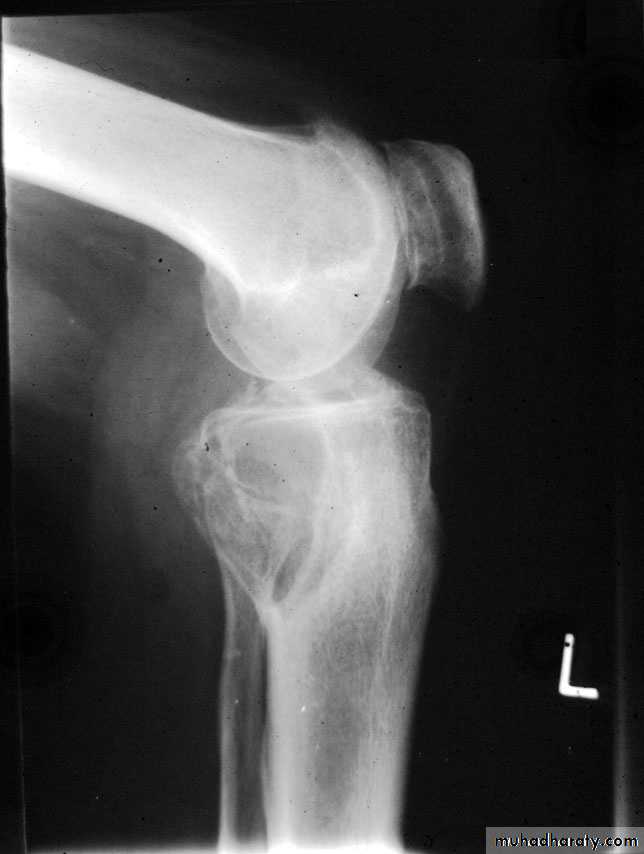

O/E vague swelling at the bone end and signs of joint irritation.X-ray:

Rarefied area of the bone end reaching just below the articular surface.Eccentric lesion with bone expansion and ballooning with cortical thinning, sometimes pathological fracture.

There may be calcific trabiculations inside the lesion giving it the commonly known saop-bubble appearance.